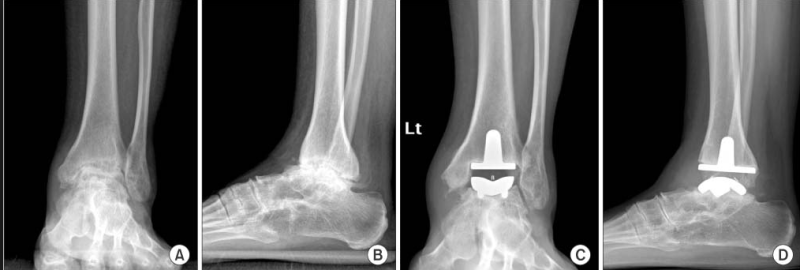

인간의 뼈와 가장 유사한 성질을 가진 금속과 마찰계수가 작은 폴리에틸렌으로 구성된 인공관절은 심하게 아프거나 딱딱해진 무릎을 새로운 관절로 교체해 통증을 없애고 관절 가동성을 확보할 수 있다. 수술이지만 무릎뿐만 아니라 발목에도. 관절염으로 인해 발목 관절이 심하게 손상되고, 통증이 너무 심해 걸을 수 없고, 약물, 물리치료 등 다른 방법으로도 해결할 수 없는 경우 인공관절 치환술을 고려할 수 있습니다. 인공관절 치환술. 과거에는 발목관절염이 심할 때 통증을 완화하기 위해 관절유합술을 시행했지만 관절유합술은 발목 관절을 구부리고 펴지 못하는 장애를 남기고 있어 큰 불편을 겪었다. 관절 교체 수술은 발목 움직임을 유지하면서 통증을 제거하는 혁신적인 대안입니다. 발은 인체에서 가장 많이 사용되는 부위로 발의 건강을 좌우한다고 합니다. 이것은 매우 중요한 부분입니다. 자주 사용하는 부품이기 때문에 쉽게 다칠 수 있지만 매우 중요한 부품이기 때문에 다치지 않도록 각별한 주의가 필요합니다. 발목이 심하게 다친 경우에는 인천모두병원에서 소개하는 인공발목관절 치환술로 치료가 가능하지만 다치지 않도록 주의하시고 수술을 피하시기 바랍니다. 발목 수술은 병원의 모든 것!부상을 당하여 어떠한 치료를 받아도 상태가 호전되지 않는다면 인천 남동구 모도병원에서 인공관절 치환술을 고려해보시기 바랍니다. 한계를 극복하기 위해 1. 최소침습수술(MIS) 기술을 이용한 개인 맞춤형 인공관절 2. 풍부한 경험을 갖춘 숙련된 의료진의 고품질 수술(정밀 절골술, 인대 균형 등) 기술 4. 수술 절개 부위가 작아(약 10cm) 회복이 빠르고 흉터가 작습니다. 발목 관절 성형술은 발목 치료의 거의 마지막 단계입니다. 모두의병원에서는 약물치료, 물리치료, 인공관절 치환술 등 비교적 간단한 치료가 가능합니다. 즉, 다양한 치료방법으로 치료가 가능하기 때문에 환자의 상태에 따라 치료를 하게 됩니다. 발목의 통증을 방치하지 마시고 인천 남동구 모두병원으로 내원하시기 바랍니다. 모두병원 인천광역시 남동구 농구애로 88